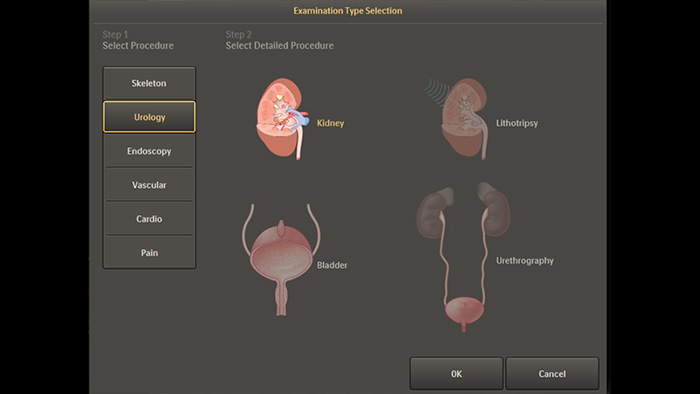

Default anatomical settings for urology and endoscopy procedures

Pre-defined imaging parameters for different procedures and anatomy, which can be customized per application, elevate clinical confidence and efficiency for each day’s diverse procedures and patients.